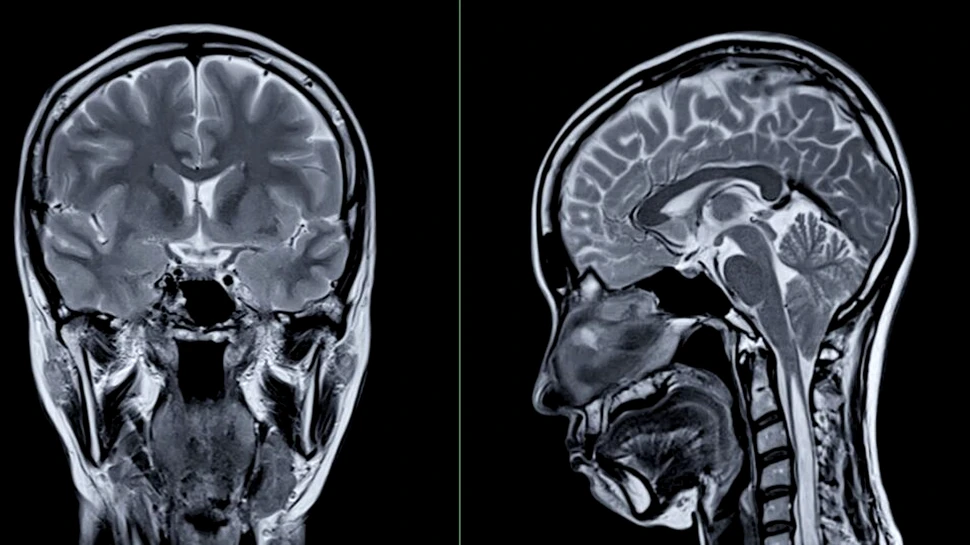

Vocile i-au spus că trebuie să intre, deoarece are două probleme: o tumoare cerebrală și o inflamație a trunchiului cerebral. Extrem de tulburată, femeia a fost supusă, la cererea medicului, unei scanări cerebrale pentru liniștire. După unele ezitări, investigația a fost aprobată, iar rezultatul a confirmat prezența unei mase compatibile cu un meningiom de mari dimensiuni.